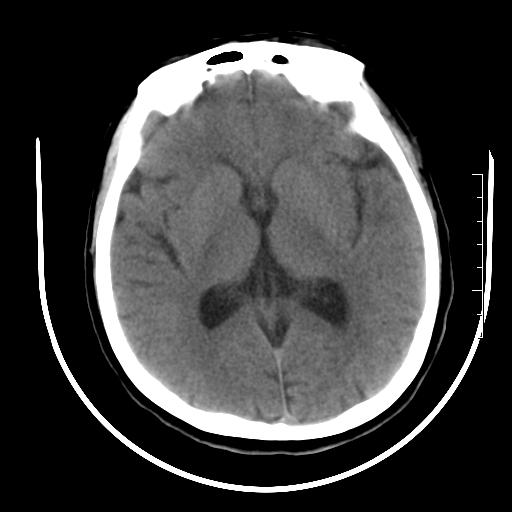

标题: CT27880:f、55y,头痛。 [打印本页]

标题: CT27880:f、55y,头痛。

考虑左侧顶部镰旁脑膜瘤;建议行ct增强扫描检查。

考虑左侧顶部镰旁脑膜瘤,建议行ct增强扫描检查。

考虑左侧顶部镰旁脑膜瘤;建议行ct增强扫描检查

大脑镰旁脑膜瘤可能,建议增强或mri

镰旁小脑膜瘤可能性大

左侧顶部镰旁脑膜瘤,增强